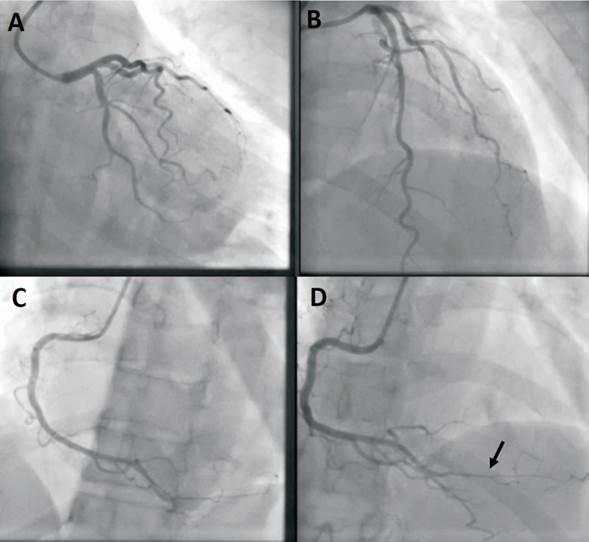

Dada la administración de potentes analgésicos que podrían enmascarar los síntomas y las nuevas alteraciones observadas en el ECG que sugieren la oclusión de un vaso epicárdico, se decide evaluar anatomía coronaria mediante cineangiocoronariografía (CACG) (figura 2). Si bien la estenosis observada sobre el ramo posterolateral podría corresponder a una disección coronaria espontánea de tipo 2a (afectación difusa del vaso con recuperación del calibre distal), los hallazgos no son concluyentes de esta entidad; no se observa, por ejemplo, tortuosidad con angulaciones próximas a 90°. Debido a la clínica (ausencia de dolor) y a lo difuso y distal de la lesión, se plantea tratamiento médico inicial y continuar evaluación en búsqueda de diagnóstico etiológico. Los ECG posteriores permanecieron incambiados. La dosificación sérica de troponinas fue negativa. Se realiza ecocardiograma transtorácico (ETT) (figura 3), que evidencia una masa probablemente intramiocárdica en región inferolateral del ventrículo izquierdo (VI).

Figura 2: Angiografía coronaria. Cateterización de la arteria coronaria izquierda en proyección caudal (A) y proyección craneal (B), sin lesiones angiográficamente significativas. La cateterización de arteria coronaria derecha en proyección oblicua izquierda(C) y proyección craneal(D) evidencia una estenosis severa y segmentaria del ramo posterolateral(flecha).

El hallazgo de una elevación del segmento ST como forma de presentación de las tumoraciones cardíacas es infrecuente y puede deberse a la compresión tumoral de una arteria coronaria o a la invasión miocárdica. Varios mecanismos a nivel celular podrían explicar la elevación persistente del segmento ST. Entre ellos, el desarrollo de una corriente de injuria secundaria a una reacción inflamatoria peritumoral; la transferencia iónica de potasio desde el tejido necrótico al miocardio adyacente lo que produce una diferencia de potencial eléctrico entre estas áreas; y, finalmente, el estiramiento de las fibras musculares adyacentes que llevan a una corriente de injuria similar a la que ocurre en el caso de los aneurismas ventriculares(2,3). En nuestro caso, la angiografía evidenció una disminución de calibre del ramo posterolateral, que podría corresponder a compresión tumoral extrínseca (figura 2). Sin embargo, no creemos que el supradesnivel-ST pueda explicarse por la compresión coronaria extrínseca. Dada la evolución electrocardiográfica, con persistencia del supradesnivel sin evolución a ondas Q y la ausencia de marcadores de necrosis miocárdica, no planteamos se trate de un cuadro de isquemia en curso. Sugiriendo fuertemente los hallazgos electrocardiográficos podrían ser secundarios a los mecanismos celulares inducidos por el tumor.